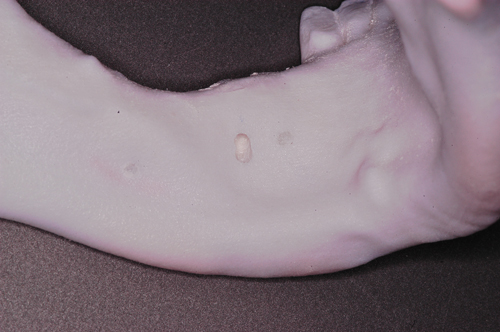

Palabras Clave: ELG: Estereolitográfico OH: Oclusión Habitual ORC: Oclusión en Relación Céntrica Paciente de 35 años de edad ,sexo masculino que lo derivan para implantar el tercer cuadrante. A la auscultación presenta ruidos articulares de tipo chasquido que remiten temporalmente luego de limitación de apertura bucal y maniobras quinesiológicas distractoras. También se observan recidivas de caries en algunos empastes y falta de disclusión canina de ambos lados. Se estudia el caso desde un punto de vista clínico, scanografico mediante Dentascan y tridimensional mediante montaje en articulador. A partir del scanner se obtienen datos para confeccionar modelo estereolitográfico (ELG),operar en el y construir férula quirúrgica dento-muco soportada. Habitualmente se procede directamente a implantar, dado que ese era el requerimiento del profesional derivante y el deseo del enfermo. Sin embargo, esa actitud enmascararía otro tipo de problemas que la boca presenta. Se consulta al odontólogo derivante, y coincide con mi opinión acerca de que si solo se lo implanta, sin corregir la posición mandibular, la situación de las ATMs, los empastes sin anatomía y la falta de disclusiones, el resultado final no será el deseado y su eficacia masticatoria no funcionará optimamente. Consultado el paciente coincide y acepta ese concepto y entonces procedemos a confeccionar un Jig de Lucia a partir del montaje de estudio, y lo dejamos puesto en boca toda la noche anterior a la consulta, para proceder a realizar un ajuste oclusal al día siguiente sin engramas anteriores, lo que facilita no tener que relajar nuevamente con laminillas de Long. En esta etapa pierde el implante correspondiente a la pieza 4.7 que traía en boca. Estabilizado el sistema, procedemos a la parte quirúrgica, comenzando por instalar la férula, retirar opérculos gingivales mediante bisturí circular, fresado óseo e instalación de implantes ,toma de impresión a cubeta fenestrada (pegando con metacrilato sin cambios dimensionales, los transfers a la cubeta especialmente diseñada.(1º método de pasividad protética utilizado), e instalación de tornillos de cicatrización. Inmediatamente de retirada la cubeta de boca y colocadas las réplicas de los implantes, procedemos a ferulizar los “ápices” de las réplicas para que no sufran movimientos durante el llenado de la impresión.(2º método de pasividad protética utilizado). Controlamos radiograficamente Tres meses después, procedemos a tomar nuevos registros de arco facial, registros intermaxilares en Oclusión en Relación céntrica, montaje de los modelos obtenidos intra operatoriamente y confección de un conjunto de cuatro coronas provisionales de metacrilato en el sector implantado y las correspondientes al maxilar superior. Verificada la perfecta función de todos los componentes, ausencia de todo tipo de síntoma y comprobada la paz en todo el sistema, procedemos tiempo después a confeccionar las fundas definitivas, que constituyen el “cerrojo” de la dinámica del mismo. Por último, corroboramos la oclusión fundamentalmente en lo que hace a la: